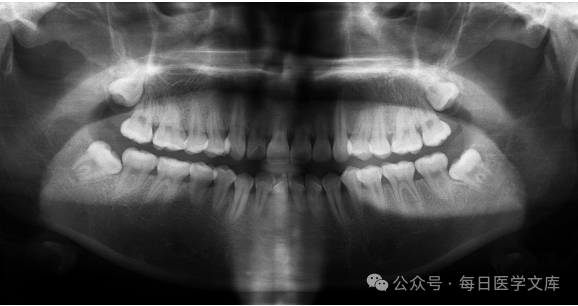

操作的核心是怎么寻找球管相对应的面部的体表标志?

上颌11:鼻尖

上颌22:鼻尖与鼻翼连线的中点

上颌33:鼻翼

上颌45:瞳孔线做一下垂线与听鼻线的交点

上颌5678:外眼角下垂线与听鼻线的交点(颧骨下缘约一个横指,相当于1厘米处)

下颌为:下颌下缘上1厘米处的假象相对应的牙齿位置上。

患者的位置:患者坐于X光机椅子上,坐直,枕部靠在头托上,使头的矢状面与地面垂直、听鼻线与地面平行。

胶片的放置位置:用普通3X4厘米牙科胶片,放置于上颌磨牙的舌腭面,胶片的短轴与上颌7的牙体长轴平行,胶片的边缘超出磨牙下10毫米左右,(留出边缘的目的是为了使胶片有良好的对比度,避免牙齿图像超出胶片。)用对侧的大拇指按压在胶片的中央位置,即为上半部,其他的四个手指扇形展开,贴附在手的同侧的面部皮肤上。

胶片焦点距离为20厘米

角度为+28度,有部分书上是+30度,使x 垂直于上颌磨牙长轴与胶片之间的角平分线,水平角度与磨牙邻面平行。

体表标志:上颌56:两眼向前平视,在瞳孔向下画出一条垂下与鼻翼耳屏连线的交叉点(颧骨的前方)

上颌78:由外眼角向下方画出一条垂线与与鼻翼耳屏连线的交叉点(颧骨的下缘)。

注意:要根据患者的身高调整椅子的高度,使患者的口角与医生的腋部相平齐,方便医生的操作。医生一般是站在被照侧的前方。